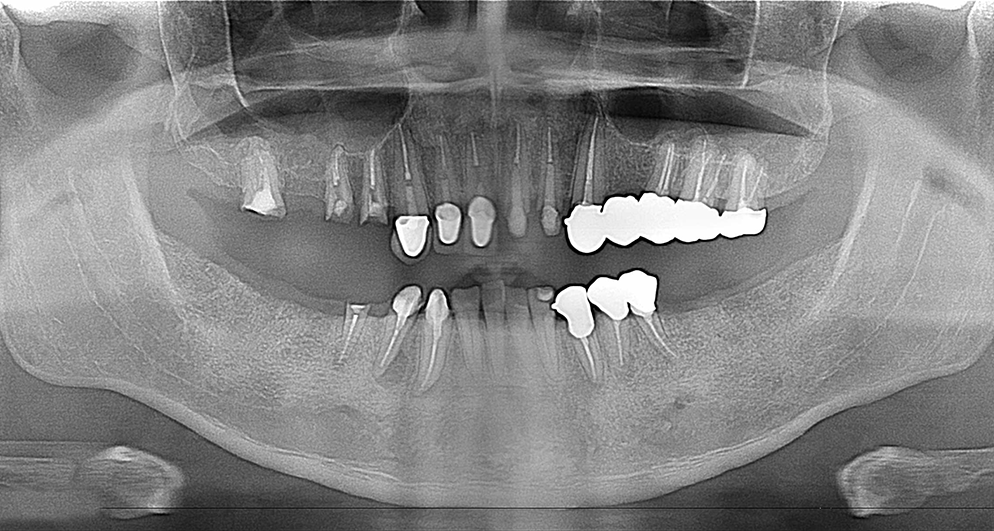

この患者様は長い事歯科医院には通っておらず、下の歯は前歯以外は全て崩壊していることが分かります。

また、奥歯がなくなってからの期間が長かったため、入れ歯が入るスペースが奥にないのが分かります。

様々なことを鑑み、患者様とも何度も話し合いを行い、下の奥歯には必要最低限のインプラントを、他の歯も外科処置を施しなるべく歯を抜かない方法を取りました。

最終的に抜歯した本数は下の歯5本。上の歯に関しては全て残すことが出来ました。